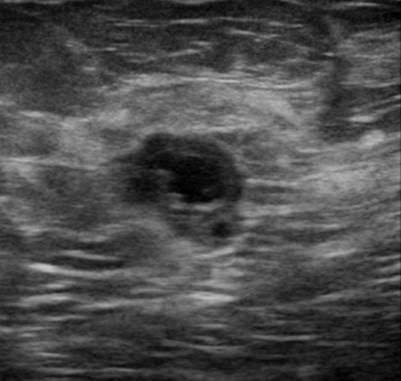

Ung thư vú - Ảnh 4

Ung thư vú

» Thông tin: Nữ giới – 50 tuổi.

» Lâm sàng: Kiểm tra sức khỏe.